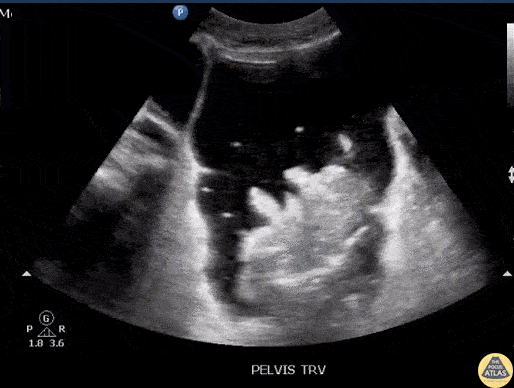

Bowel-GI - Ascites with Pneumoperitoneum

Pt with PMH of cirrhosis presents with abdominal pain and fever. POCUS initially performed for diagnostic paracentesis in the setting of suspected spontaneous bacterial peritonitis. Imaging demonstrated bubbles seen in ascites fluid consistent with pneumoperitoneum. This led to management change as paracentesis was deferred and surgery was consulted. The patient was taken to the OR, and found to have a diverticular abscess with a necrotic segment that was resected. Image courtesy of Robert Jones DO, FACEP @RJonesSonoEM Director, Emergency Ultrasound; MetroHealth Medical Center; Professor, Case Western Reserve Medical School, Cleveland, OH View his original post here